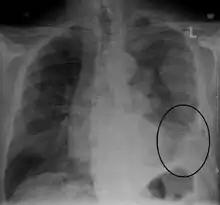

| CT scan showing a left sided mesothelioma with an enlarged mediastinal lymph node | |